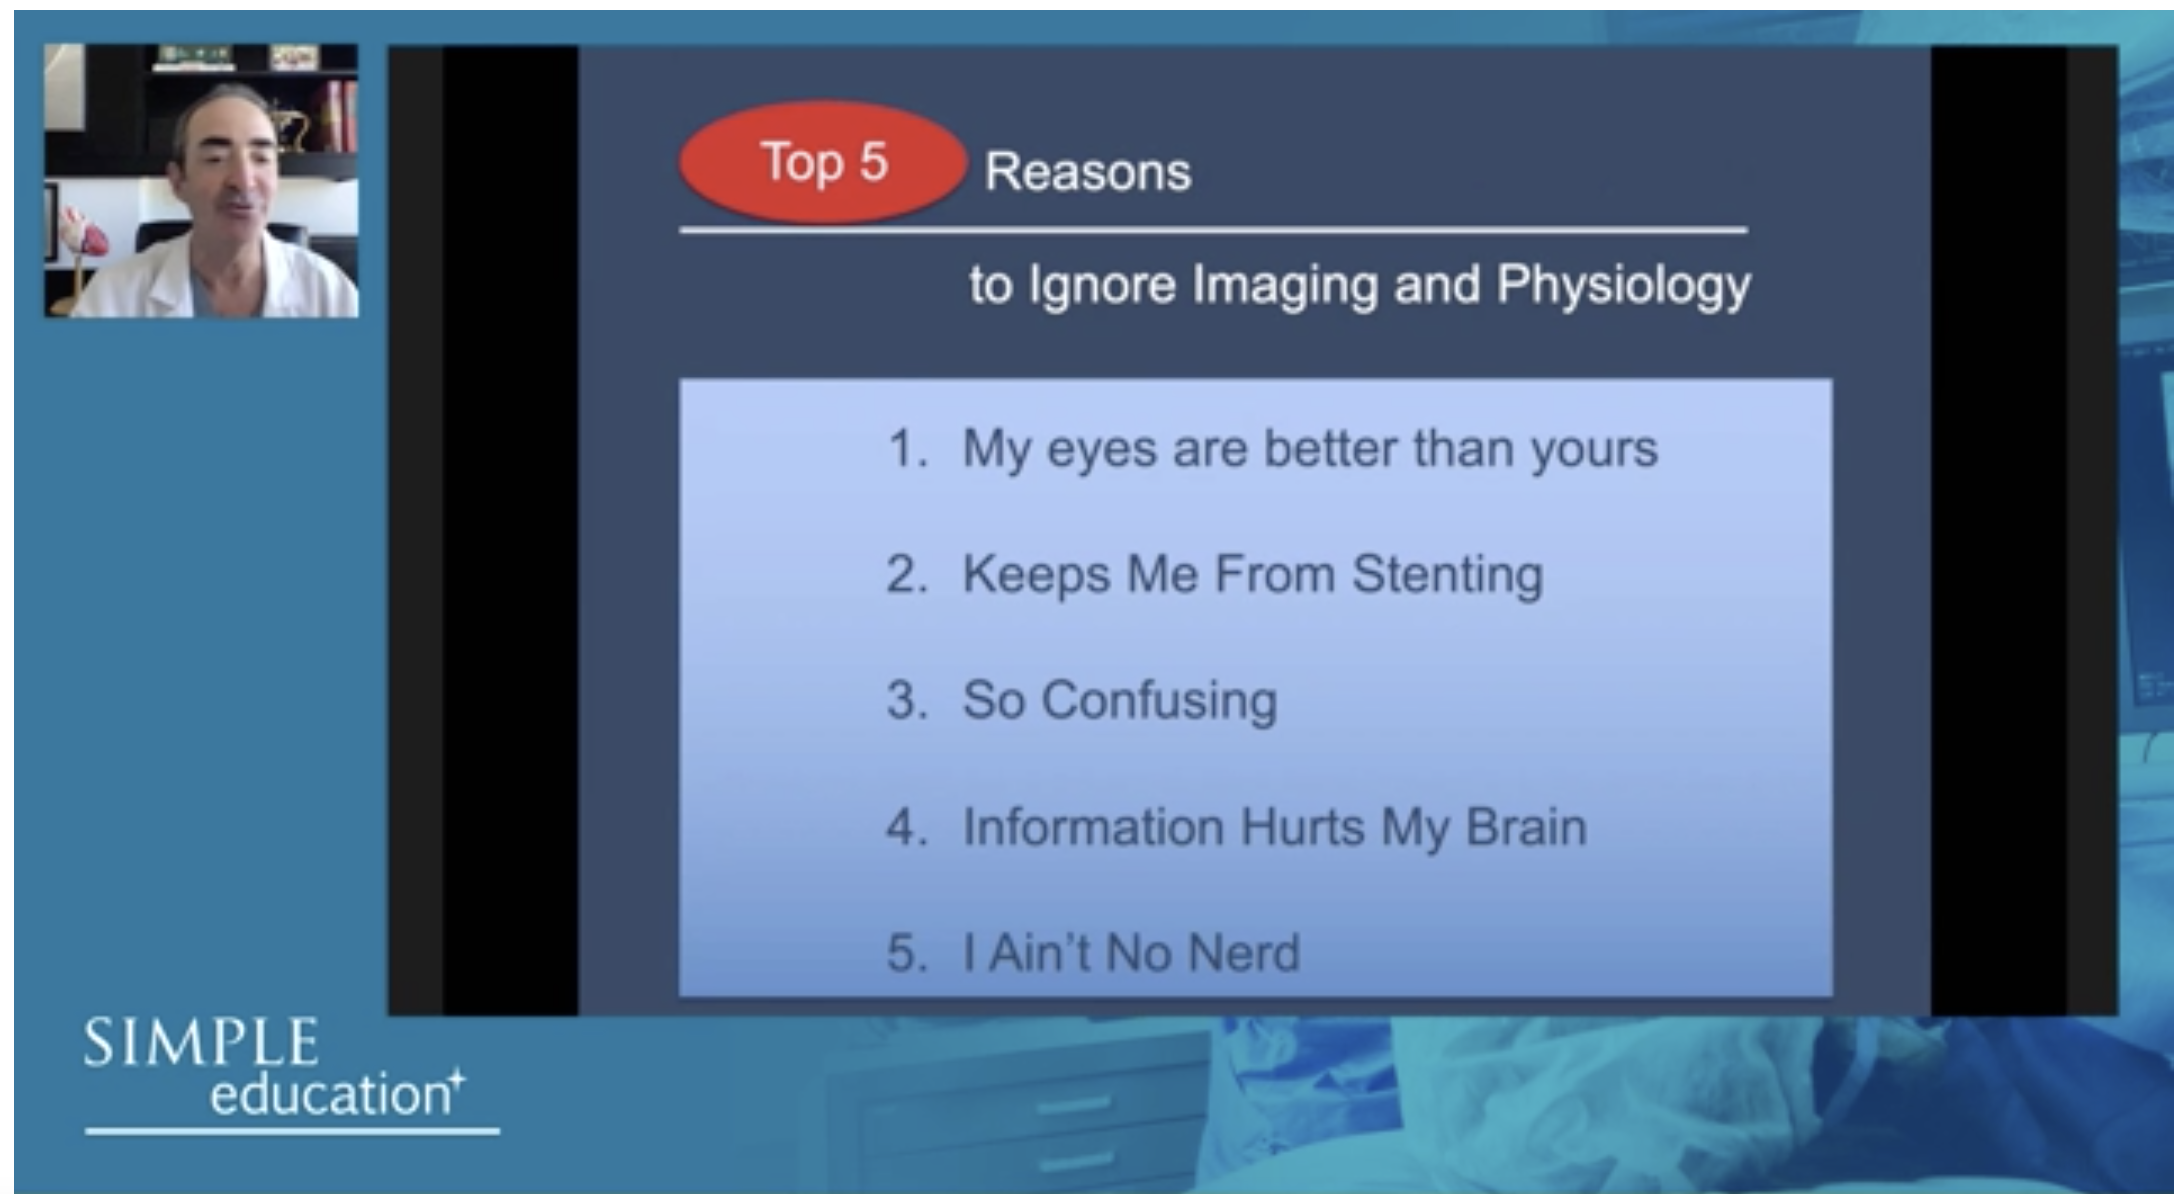

Welcome & Applied coronary physiology to plan and guide PCI-2023 EAPCI Consensus

20 year overview of clinical trial data to support the use of coronary physiology in revascularisation decision-making

Essential steps for physiology-based PCI planning and guidance - Dr Allen Jeremias